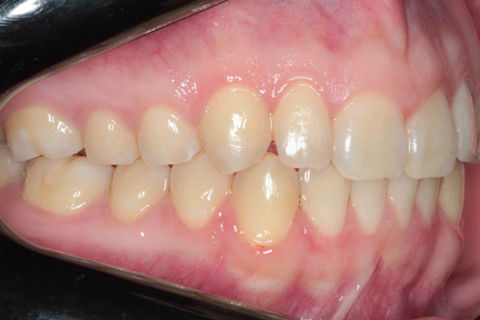

Inicial L. Dir

Inicial L. Esq

Final L. Dir

Final L. Esq